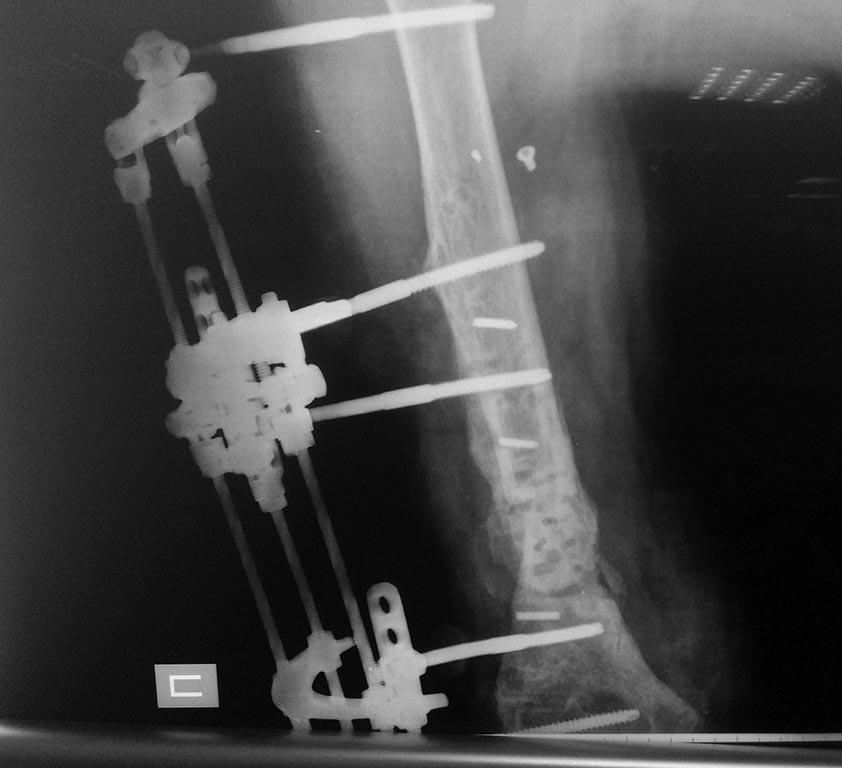

5 месяцев с АВФ